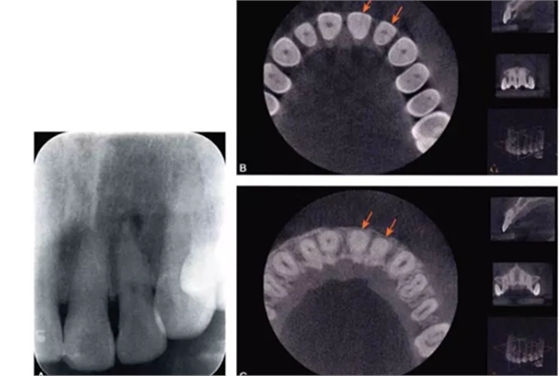

完全鈣化根管在X線片上的表現(xiàn)是根管影像模糊,密度增高,根管密度與周圍的牙本質(zhì)密度接近,甚至無法區(qū)分根管與牙本質(zhì)的影像。有些根管,可表現(xiàn)為根管影像時斷時續(xù)或模糊不清,為不完全鈣化根管表現(xiàn)(圖4-1A)。細小根管的病例在X線片上,根管影像隱約可見,與同名牙或鄰牙相比,根管較為細小影像清晰度降低。

目前,小視野CBCT物理層厚可達76m,對根管系統(tǒng)的顯示明顯優(yōu)于其他影像學(xué)手段。觀察根管的CBCT圖像,冠根向橫斷面能夠比較直觀地顯示根管中央的鈣化情況。觀察時可從髓底開始,將橫截面斷層由冠方向根尖方向推移,逐層觀察。正常根管位于牙根的中央部位,呈圓形或橢圓形暗影,與周圍的牙本質(zhì)所顯示的致密白色影像有明顯區(qū)別。細小鈣化根管表現(xiàn)為橫截面中央的暗影變淡、消失,與周圍牙本質(zhì)影密度接近或相同,與同一患牙其他根管及正常鄰牙的根管影像則有明顯區(qū)別。通過CBCT,還可以測量鈣化根管的長度及范圍(圖4-1B、C)。